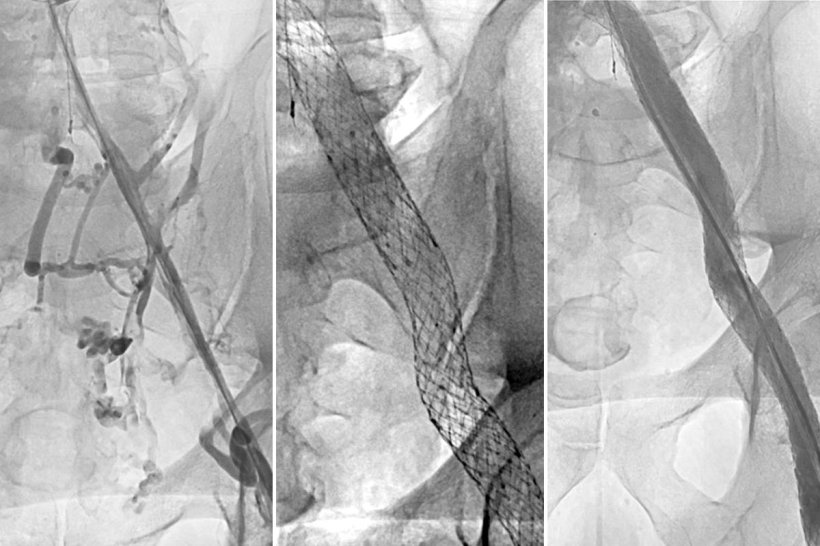

Image source: WashU Medicine; courtesy Suresh Vedantham

The study enrolled 225 patients at 29 sites across the U.S. who had been treated for deep vein thrombosis for at least 3 months and had blockage of the iliac vein (a major vein in the pelvis) causing substantial disability. Patients were chosen at random to receive either a stent — a mesh tube inserted into the vein to reinforce and expand it — plus standard treatment with compression and blood-thinning medications, or standard treatment alone. A stent is placed in a two-to-three-hour operation that requires only tiny incisions.